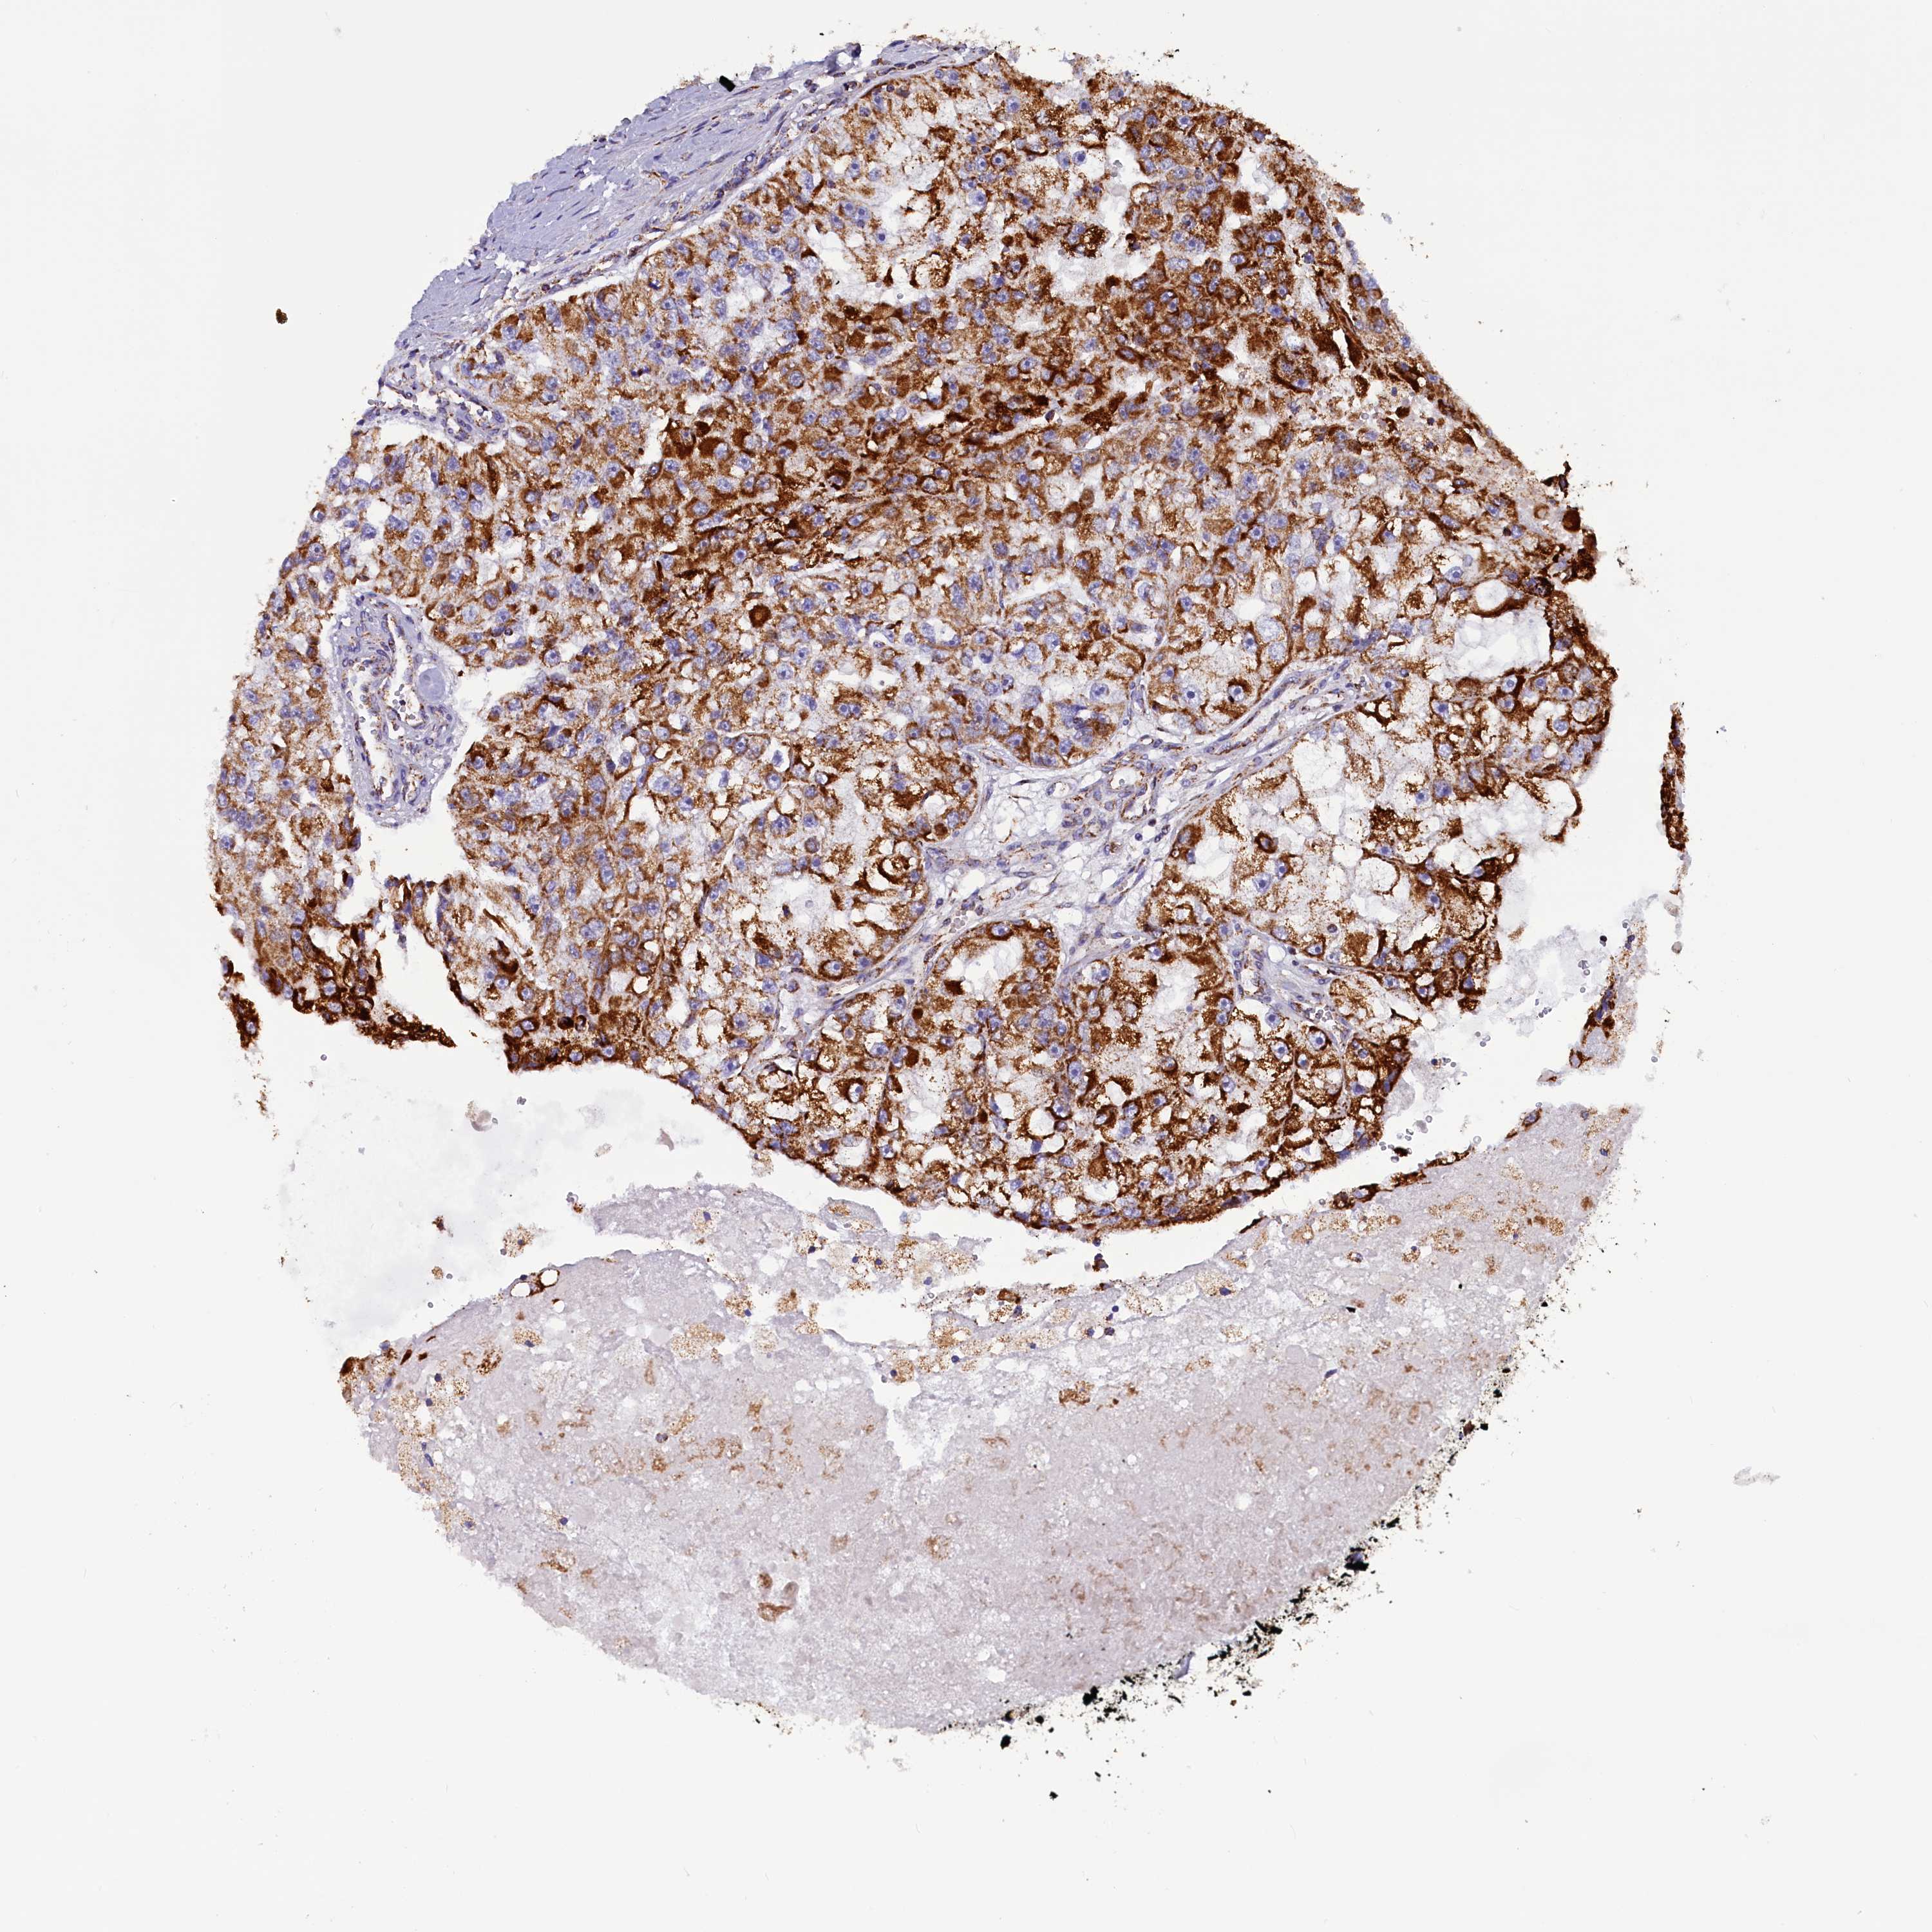

KIDNEY RENAL CLEAR CELL CARCINOMA (TCGA) - Interactive survival scatter ploti

The Survival Scatter plot shows the clinical status (i.e. dead or alive) for all individuals in the patient cohort, based on the same data that underlies the corresponding Kaplan-Meier plots. Patients that are alive at last time for follow-up are shown in blue and patients who have died during the study are shown in red.

The x-axis shows the expression levels (FPKM) of the investigated gene in the tumor tissue at the time of diagnosis. The y-axis shows the follow-up time after diagnosis (years). Both axes are complimented with kernel density curves demonstrating the data density over the axes. The top density plot shows the expression levels (FPKM) distribution among dead (red) and alive patients (blue). The right density plot shows the data density of the survived years of dead patients with high and low expression levels respectively, stratified using the cutoff indicated by the vertical dashed line through the Survival Scatter plot. This cutoff is automatically defined based on the FPKM cutoff that minimizes the p-score. The cutoff can be changed by dragging the vertical line or by entering a cutoff value in the square labeled "Current cut-off".

Under the Survival Scatter plot the p-score landscape (black curve; left axis) is shown together with dead median separation (red curve; right axis). Dead median separation is the difference in median mRNA expression between patients who have died with high and low expression, respectively. It is calculated as follows: median FPKM expression of dead patients with high expression - median FPKM expression of dead patients with low expression. This is intended to aid the user in visually exploring custom cutoffs and the associated p-scores and dead median separation.

Individual patient data is displayed and can be filtered by clicking on one or more of the category buttons on the top of the page. Categories describing expression level and patient information include: high, low, alive, dead, female, male and tumor stages. The scale of the x-axis can be toggled between linear and log-scale by clicking on the "x log" button. Mouse-over function shows TCGA ID, patient information and mRNA expression (FPKM) for each patient.

& Survival analysisi

Kaplan-Meier plots summarize results from analysis of correlation between mRNA expression level and patient survival. Patients were divided based on level of expression into one of the two groups "low" (under cut off) or "high" (over cut off). X-axis shows time for survival (years) and y-axis shows the probability of survival, where 1.0 corresponds to 100 percent.

SLC39A3 is not prognostic in Kidney Renal Clear Cell Carcinoma (TCGA)

Best expression cut offi

Based on the FPKM value of each gene, patients were classified into two groups and association between prognosis (survival) and gene expression (FPKM) was examined. The best expression cut-off refers the FPKM value that yields maximal difference with regard to survival between the two groups at the lowest log-rank P-value. Best expression cut-off was selected based on survival analysis .

When clicking on this number, the vertical dashed line indicating cut-off, the interactive survival plot, and the Kaplan-Meier curve will be adjusted to show results based on the best expression cut-off.

: 21.11

TCGA RNA samplesi

RNA-seq data is reported as average FPKM (number Fragments Per Kilobase of exon per Million reads), generated by the The Cancer Genome Atlas (TCGA) .

Normal distribution across the dataset is visualized with box plots, shown as median and 25th and 75th percentiles. Points are displayed as outliers if they are above or below 1.5 times the interquartile range. FPKM values of the individual samples are presented next to the box plot.

Average pTPM 21.3

Number of samples 521